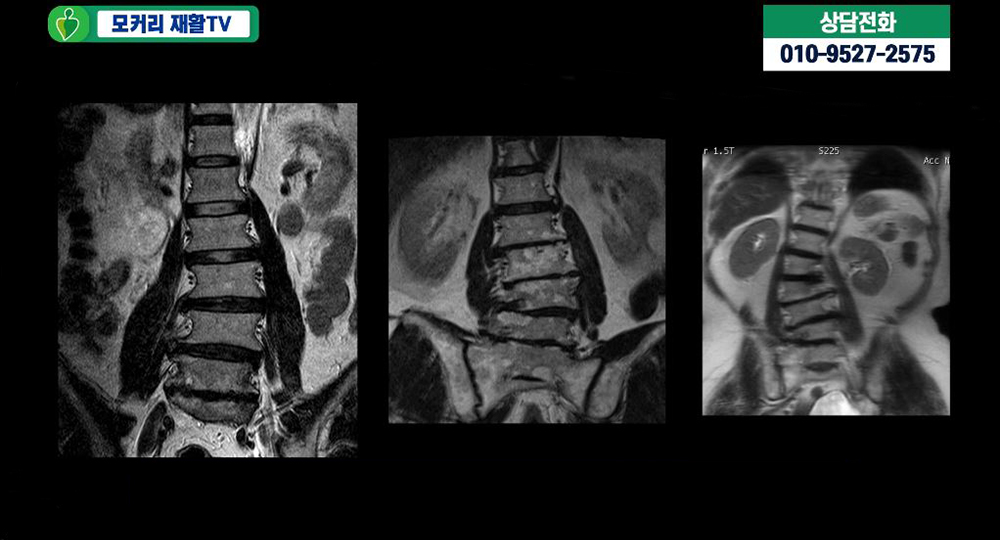

그래서 협착증을 오래 앓은 70대 이후 환자들의 척추 X-ray나 MRI를 보면 보시다시피 척추가 다 휘면서 보상성 측만이 생기는 경우가 거의 대부분입니다. 이런 것들이 신경학적 증상을 더 심하게 만듭니다.